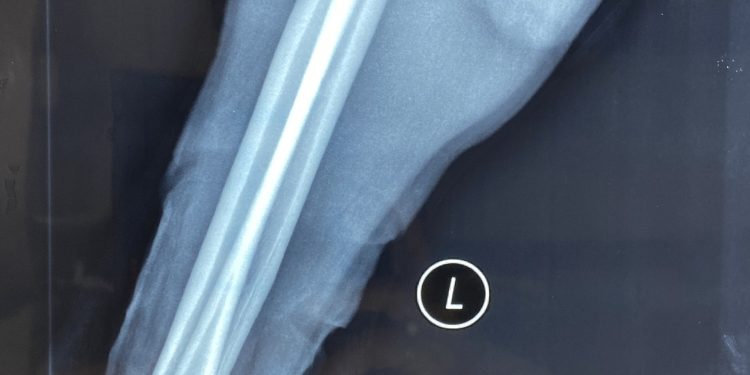

Lúc 22h30 ngày 19/7/2021, Trung tâm Chấn thương Chỉnh hình – Bỏng (TT CTCH- Bệnh viện Đa khoa tỉnh Khánh Hòa tiến hành khâu nối vi phẫu thành công ca vết thương đứt lìa cổ tay trái. Ca vi phẫu thuật kéo dài đến 7h00 sáng 20/7/2021. Vào phẫu trường, bàn tay đứt lìa được làm sạch, sau đó phẫu thuật viên chính BSCKI.Trần Ngọc Khanh và Ths.BS Lê Minh Hoan cùng Ths.BS Lê Thanh Minh đã tiến hành kết hợp xương bằng 2 đinh Kirschner, khâu nối vi phẫu bó mạch trụ quay và thần kinh giữa, khâu nối các tĩnh mạch, lấy tĩnh mạch hiển chân phải ghép 4 tĩnh mạch mu tay và nối trực tiếp một tĩnh mạch. Kiểm tra máu hồi lưu tốt, bàn tay trái được tưới máu tốt. Tiếp tục khâu nối các gân trừ gân gấp chung nông các ngón, gân gan tay dài, gân duỗi ngón cái dài và gân duỗi cổ tay trụ.

Sau phẫu thuật bàn tay được sưởi ấm, các ngón tay hồng, đã mấp máy được các ngón tay.